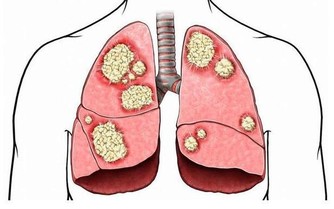

若有自體免疫疾病,如類風濕性關節炎、系統性紅斑狼瘡等,則須配合同時治療;